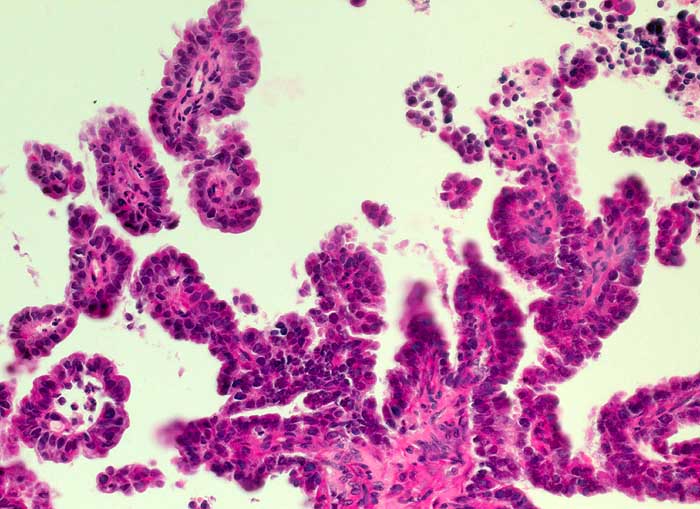

seröses papilläres Adenokarzinom des Endometrium

Plumpe Papillen ausgekleidet von einem kubischen einreihigen Epithel mit hochgradig atypischen Kernen.

St.n. Hysteroskopie, Curettage und Endometriumresektion wegen postmenopausaler-Blutung. Hoch aufgebautes Endomometrium.

200